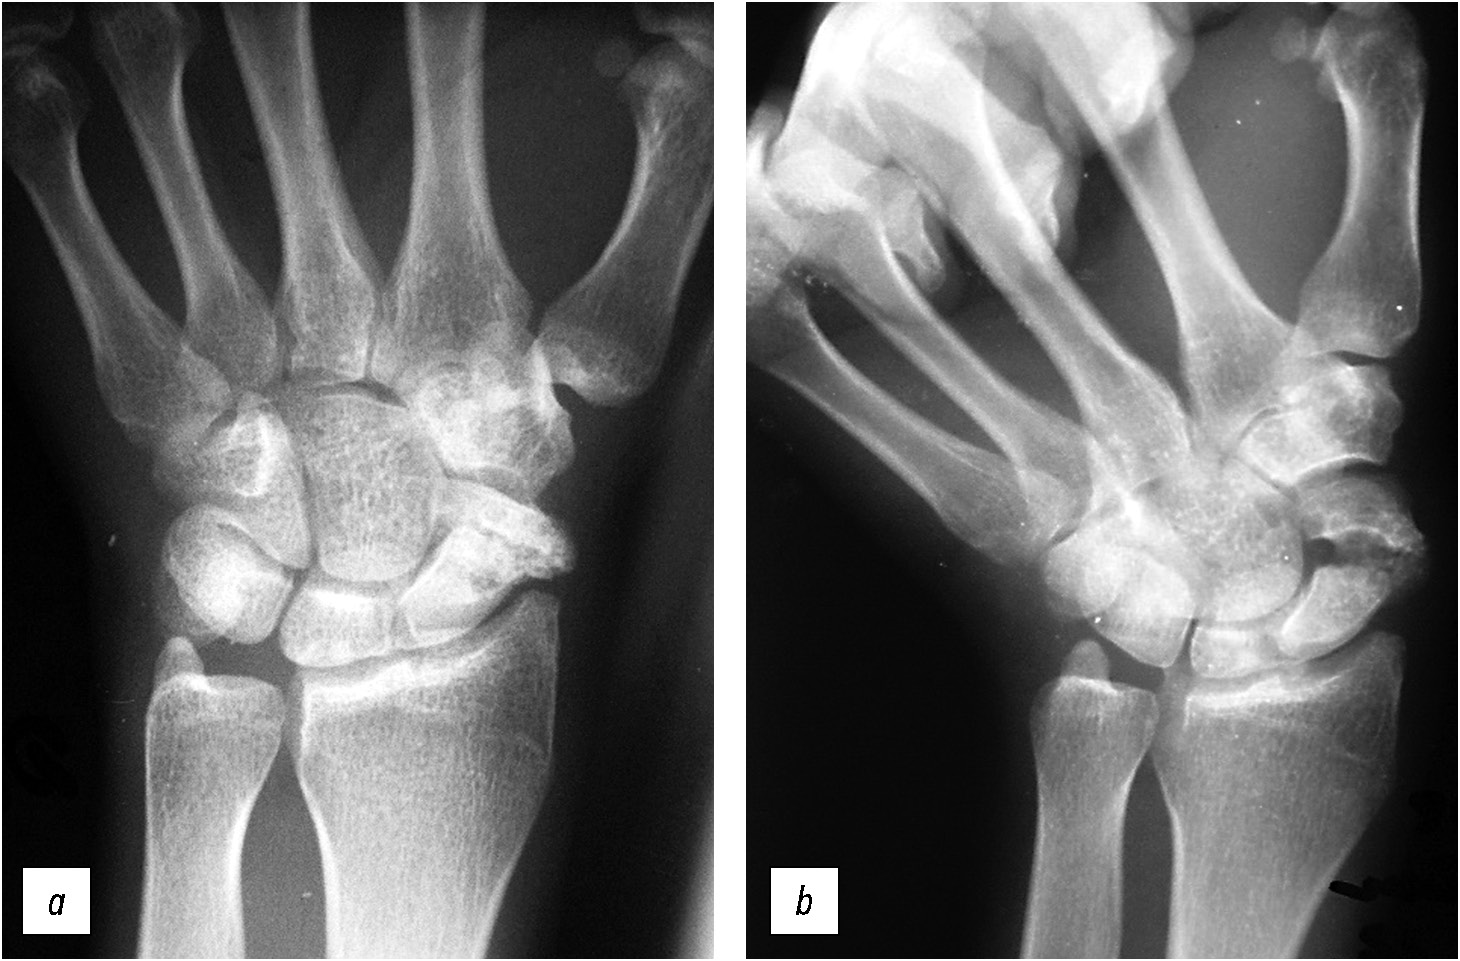

Со времени публикации W.R. Stecher прошло около 90 лет. Оригинальная авторская методика не утратила актуальности и является полезным дополнением к рутинному рентгенологическому исследованию, так как до 20–30% свежих переломов не обнаруживается на стандартных рентгенограммах [3, 4]. Способ Stecher помогает не только в диагностике острой травмы — он полезен и при планировании операции, оценке процесса консолидации перелома или ложного сустава ладьевидной кости на этапах лечения [3]. В отличие от стандартных рентгенограмм данный метод помогает определить истинный размер дефекта кости, степень деформации, состояние суставных поверхностей (рис. 6, 7).

Рис. 6. Рентгенограммы кистевого сустава пациента 22 лет: а — стандартная укладка, b — рентгенография по Stecher, модифицированный вариант (SM): выявлен ложный сустав ладьевидной кости со значительным дефектом кости.

Fig. 6. Radiographs of the wrist joint of a 22-year-old patient: а — standard position, b — radiography according to Stecher, modified version (SM): a scaphoid nonunion with a significant bone defect was detected.